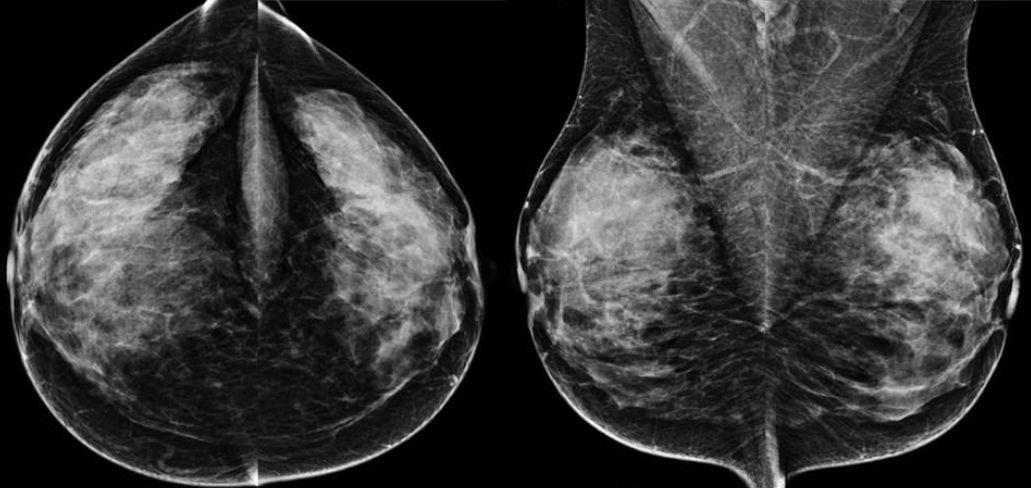

Kontrastmittel-Mammographie: Low-Energy-Bild

Kontrastmittel-Mammographie: Rekombinationsbild